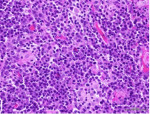

Histologic examination of the specimen from the attached gingiva exhibited erosion of the surface epithelium and supporting intense inflammatory cell infiltrate, predominantly composed of plasma cells (Figure 2). The specimen was covered by fibrinous deposits and supported superficial dilated blood vessels engorged with erythrocytes interspersed by occasional vertical streaks of residual epithelial cells exhibiting uniform basophilic nuclei surrounded by variable amounts of eosinophilic cytoplasm. With an indistinct basal layer, the lamina propria supported an intense inflammatory cell infiltrate, chiefly consisting of densely packed sheets of plasma cells with their characteristic eccentric basophilic nuclei with cartwheel-appearing chromatin surrounded by eosinophilic cytoplasm with paranuclear clear zones (Figure 3). The specimen obtained from the left maxillary gingiva presented with severe chronic mucositis with predominant plasma cell infiltrate, epithelial erosion, and stromal eosinophilia, consistent with PCG. The presence of stromal eosinophils is consistent with allergy-based gingival inflammation.22,23 None of the specimens presented with evidence of neoplasia or granulomatosis. The clinical presentation and histopathological features led the authors to a diagnosis of PCG.